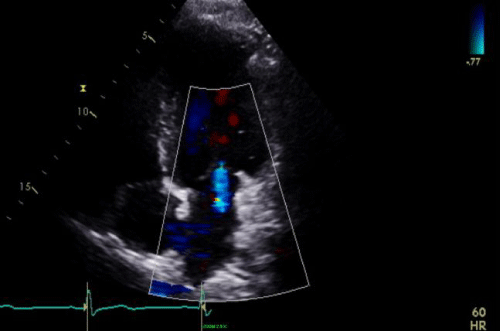

Cine 2: Sinus rhythm (SR) with VR approximately 42 bpm. Transthoracic echocardiogram (TTE) demonstrating mild (central) MR with color flow

Cine 4: SR with VR = 66 bpm

TTE apical 4-chamber view demonstrating trace TR with color flow